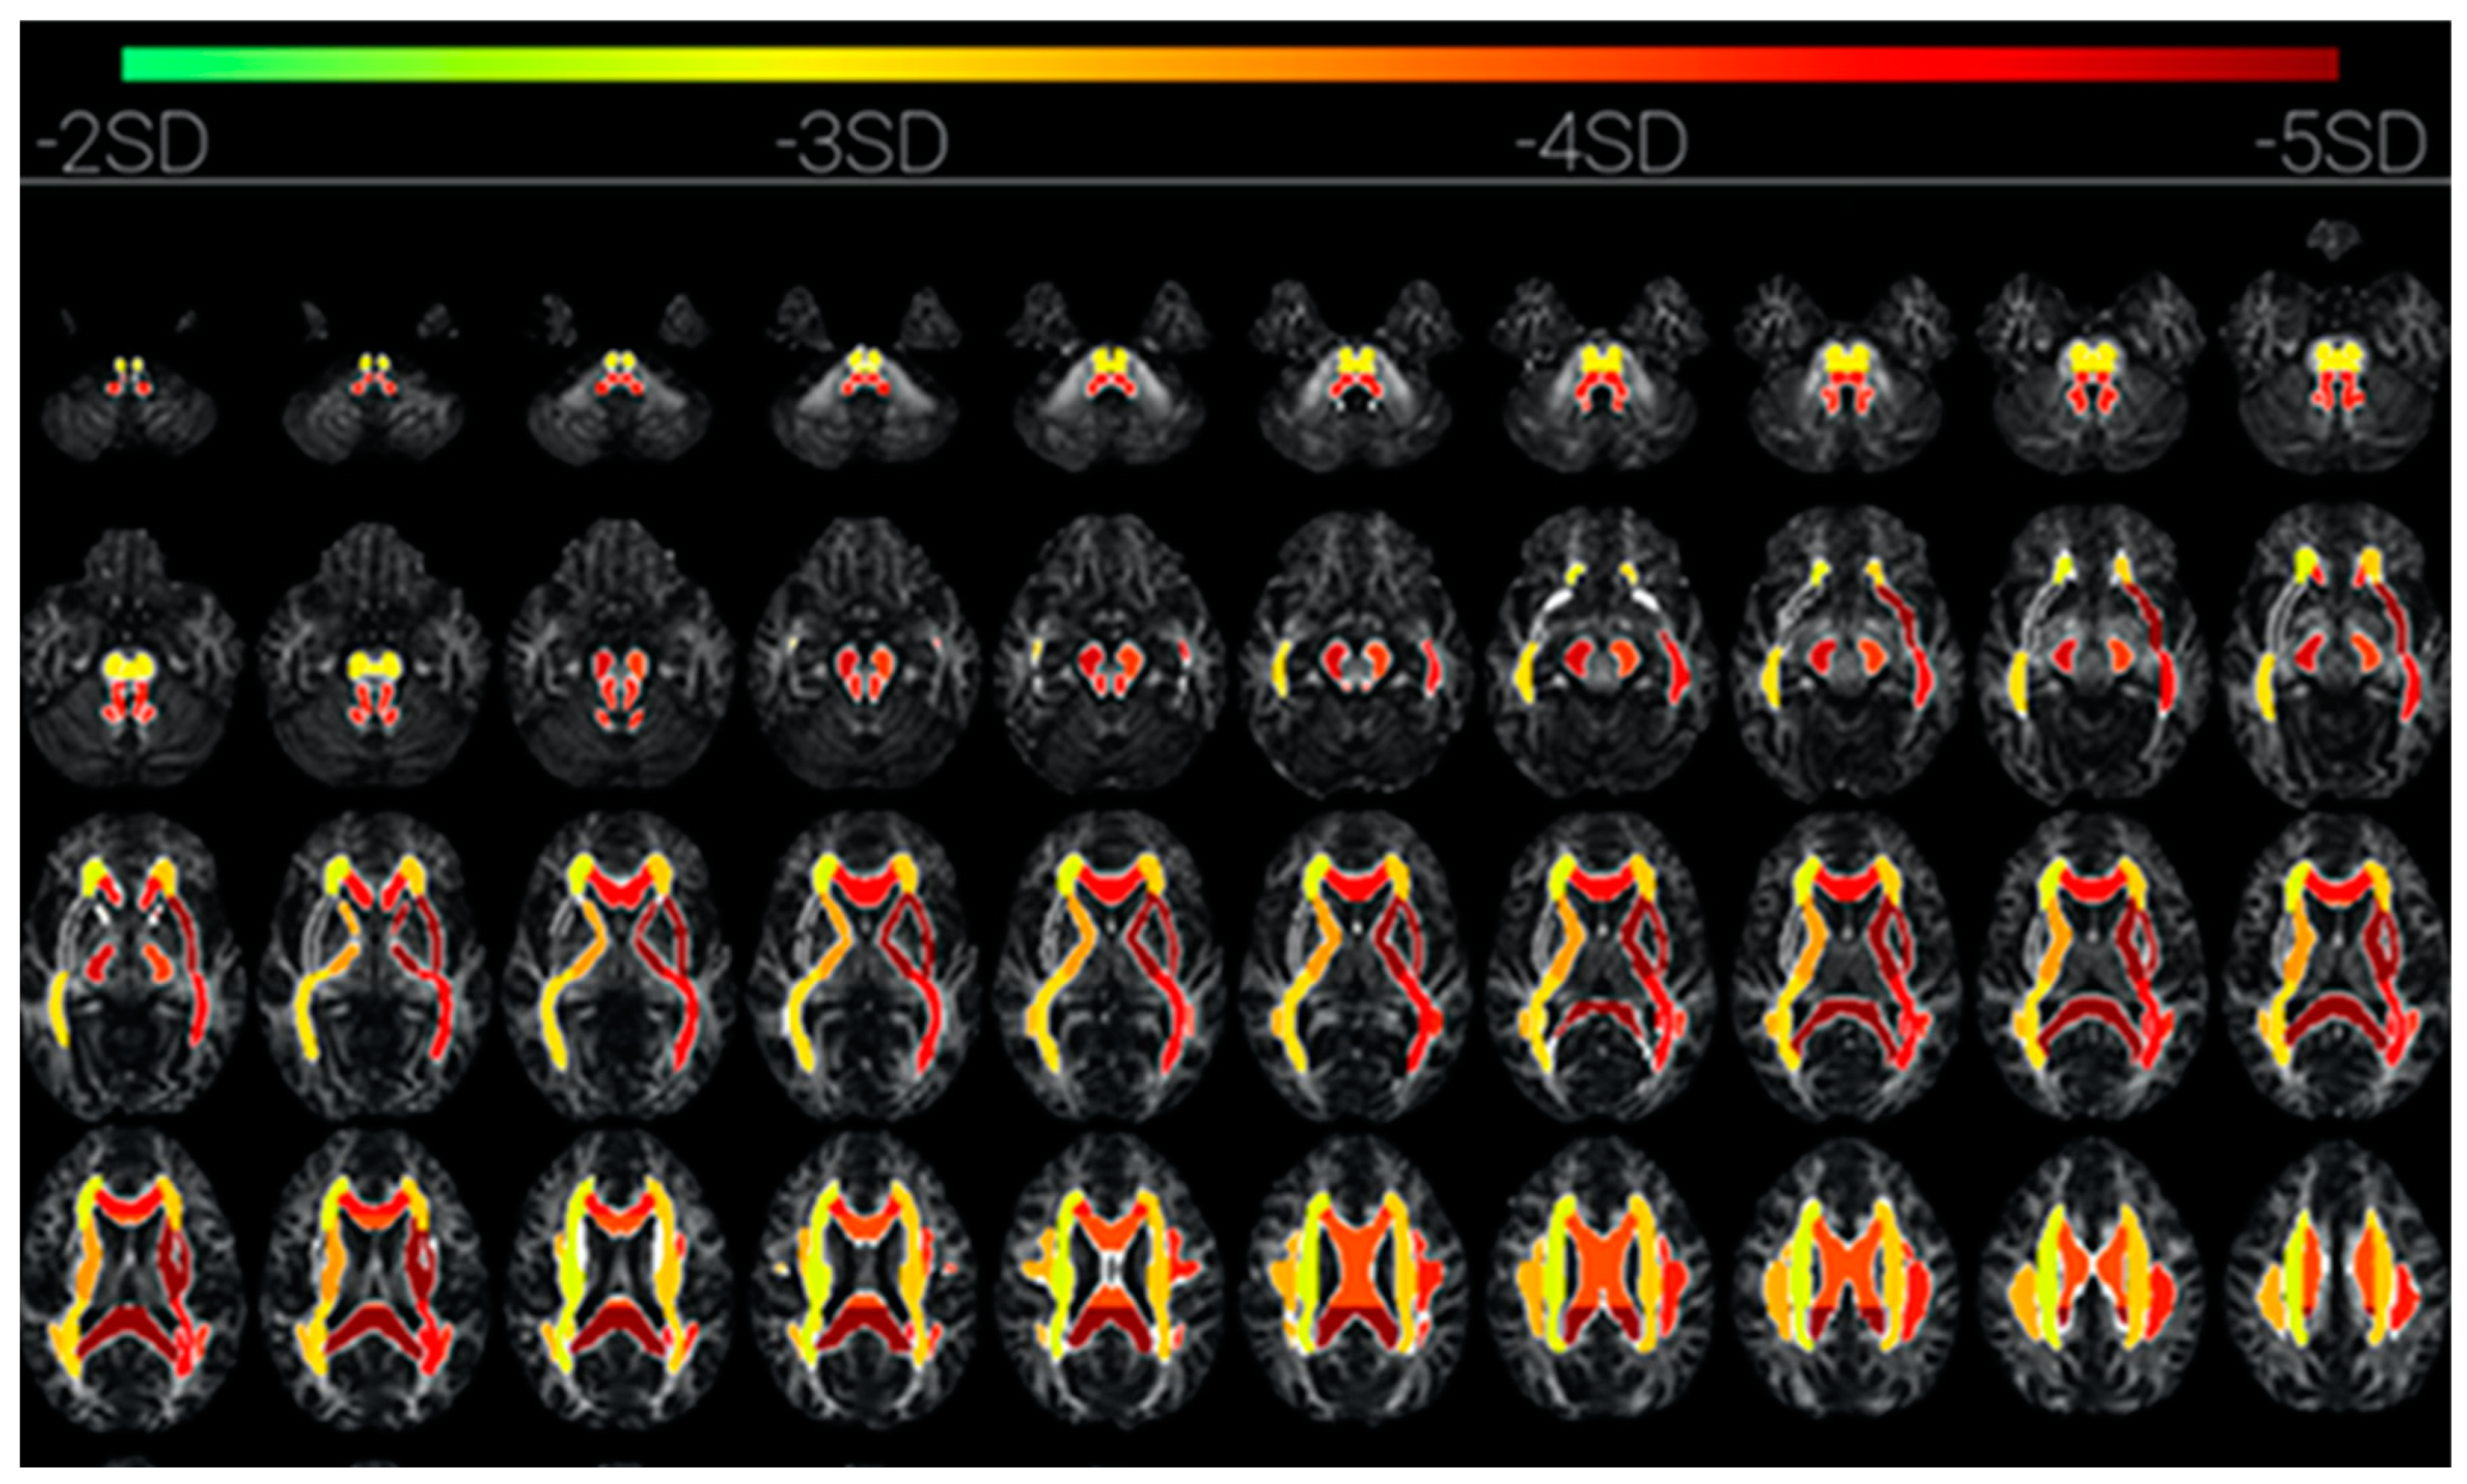

Some of these other structures that are revealed by diffusion tensor imaging (DTI) in cases of prolonged loss of C* due to COVID-19 encephalitis [51] are the subcortical pathways of the corona radiata, superior longitudinal fasciculus, anterior and posterior limb of internal capsule, and external capsule. These are interlaminar subcortical structures linking the intralaminar thalamic nuclei and ventral striatum with the limbic structures of the basal ganglia and the claustrum [52]. These structures are visualized in Figure 7 by the change in fractional anisotropy of the DTI during the loss-of-consciousness episode (Figure 2 from [51]). This mapping may be taken as an overview of the subcortical network involved in C* (although not all components would necessarily be involved, since shutting down the core C* would also deactivate dependent components of the complex). In the searchlight metaphor, switching off the source of the searchlight would also switch off the light beam and the illumination of the target object.

Figure 7. The subcortical network of reduced fractional anisotropy in a patient with prolonged loss of C* (from [51]). Strongest activation is dark red. Upper two rows: brainstem structures; middle row: predominantly the internal and external capsules, plus the splenium; lowest row: predominantly the corpus callosum.